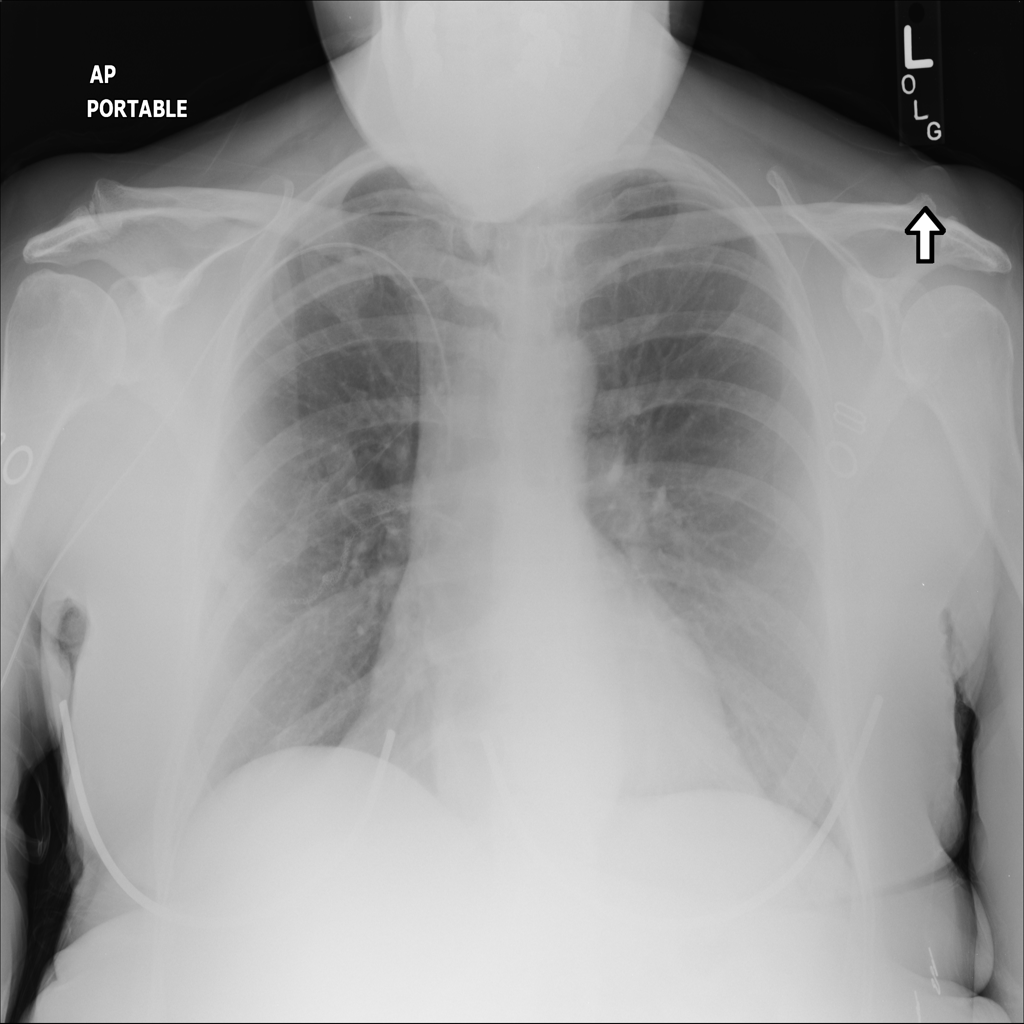

PAT-0ABD · IMG-000Hernia

PAT-0ABD · IMG-000

PA